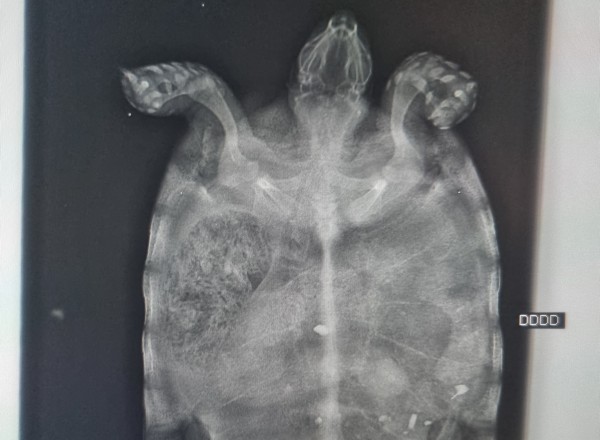

La radiographie est une technique qui utilise les rayons X. Elle est très utile dans de nombreuses situations :

- Exploration osseuse et articulaire : fractures, luxations, dysplasies hanche et coude, recherche de souris articulaire, lésions cartilagineuses, mise en évidence d'ostéomyélite, tumeurs osseuses, arthrose, ...

- Exploration abdominale :

- Appareil génital : suivi lors de gestation (dénombrement de chiots/chatons avant mise-bas), pyomètre, ...

- Appareil urinaire : recherche de calculs, anomalie rénale, d'uretère ectopique avec produit de contraste, ...

- Appareil digestif : en urgence lors de syndrome dilatation/torsion, occlusion, corps étranger, ...

- Tout autre anomalie d'un organe abdominal

- Exploration thoracique :

- Appareil respiratoire : visualisation du parenchyme pulmonaire et des anomalies pouvant y être associées (présence d’œdème, anomalies de la trachée/des bronches, nodules pulmonaires...)

- Appareil cardio-vasculaire : visualisation de la silhouette cardiaque et des vaisseaux thoraciques